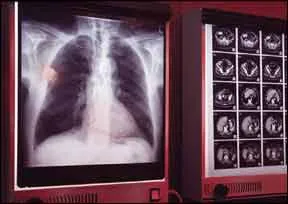

Implantable cardioverter defibrillators (ICDs) can improve the quality of life for many heart patients, but a number of misconceptions and questions surround the devices. Cardiologists are often asked questions like, "Will my cell phone ruin my ICD?" or "What about metal detectors at airports?" We asked Cleveland Clinic cardiologist Thomas J. Dresing, MD, what people should know about living with an ICD. ICDs are small devices, about the size of a pager, that are placed below the collarbone and continuously monitor the hearts rhythm. If the heart beats too quickly, the ICD issues a lifesaving jolt of electricity to restore the hearts normal rhythm and prevent sudden cardiac death.